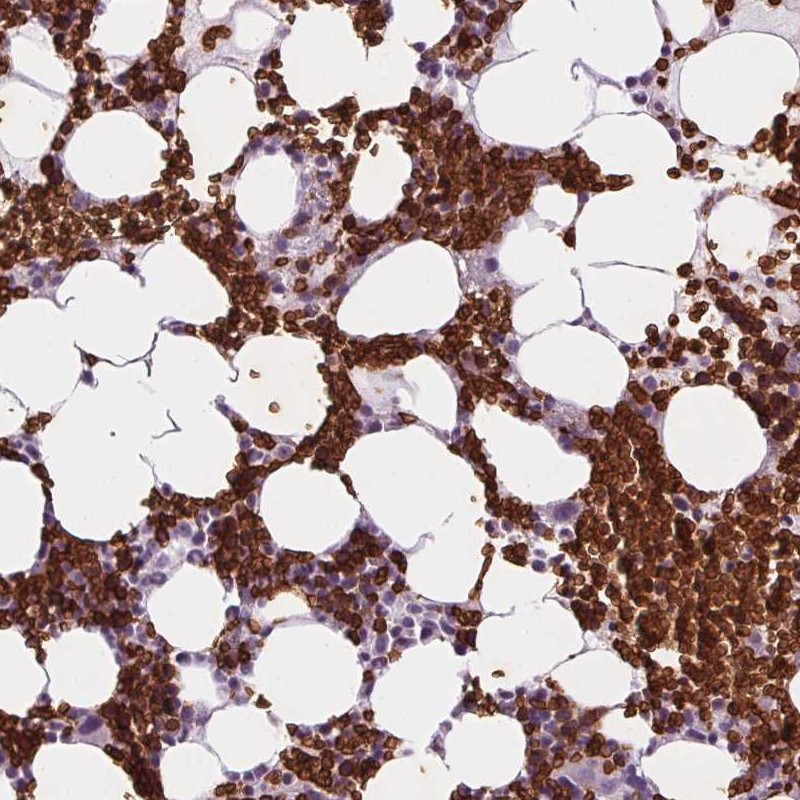

Immunohistochemistry analysis in human bone marrow and cerebral cortex tissues using Anti-SLC4A1 antibody. Corresponding SLC4A1 RNA-seq data are presented for the same tissues.